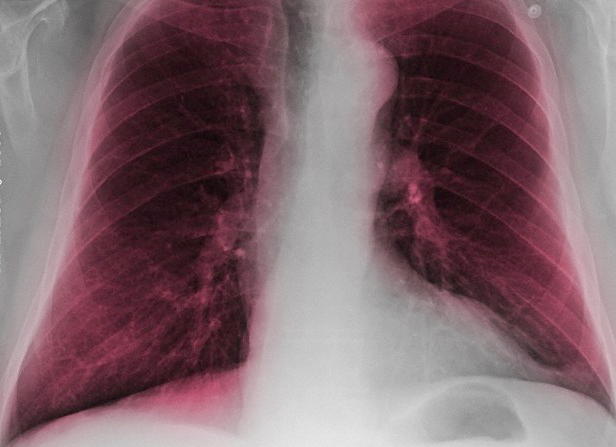

COPD is a serious lung disease that includes chronic bronchitis – resulting from constantly inflamed and irritated airways in the lungs – and/or emphysema – resulting from damage to small air sacs and airways in the lungs. In COPD patients, the airways in their lungs are partially blocked, making it difficult to get air in and out, or breathe, and get the oxygen they need.